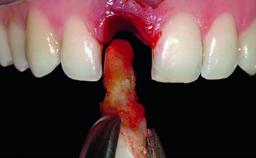

Replacement of a Failing Upper Right Central Incisor, Ridge Preservation and Late Placement of a NC Bone Level Implant

A 30-year-old patient presented at our clinic with a chief complaint of pain in her endodontically treated right maxillary central incisor (tooth 11) with a post-and-core and a fixed single crown. She had a very high lip line, a medium to thin soft-tissue phenotype, and a medium scalloped gingival contour. She also had high esthetic expectations because of her young age and beautiful smile. However, her expectations were realistic and she understood the risks of the treatment. At the initial clinical examination there was a slight mobility of tooth 11; no fistula was observed. The patient also had a single crown on the adjacent tooth 21. Both restorations were old and esthetically deficient. A digital periapical radiograph showed a very small periapical radiolucency, a thick intraradicular post, and no separation between root fragments.